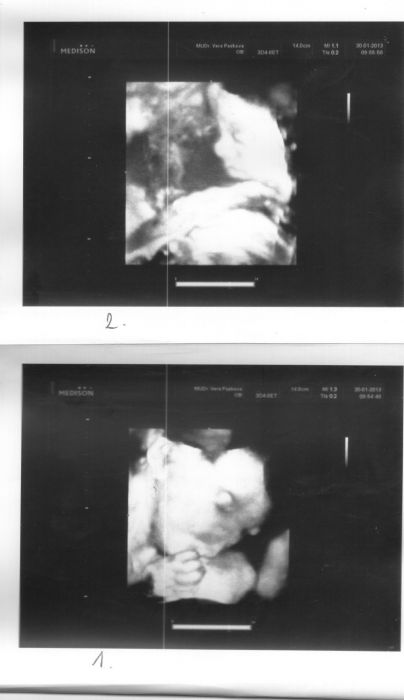

Ahoj holky,no ja už tu nebyla ,že nevím kde mám začít číst!!jinak ja už jsem v 28týdnu a mimiška mají asi 1200g každé tak to je supr jinak se cítim jako tank..A taky doufám že tam ještě dlouho vydrží!!jinak až to tu pročtu tak napíšu ..Zasílam fotto mimi čauky se bbrzo ozvu